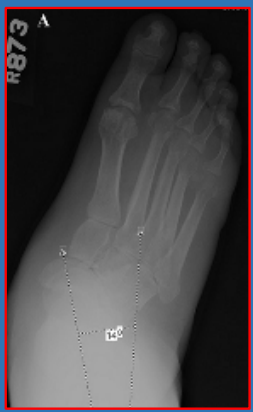

21 前足—拇外翻

拇外翻角Hallux valgus angle,HVA(metatarsophalangeal angle,MTP-1)

正常 < 15°

轻度 < 20°

中度 20°~40°

重度 > 40°

第一、二跖骨间角Intermetatarsalangle,IM 1-2

正常 < 9°

轻度 9°~11°

中度 11°~16°

重度 > 16°

跖骨远端关节角(DMAA)正常<8°